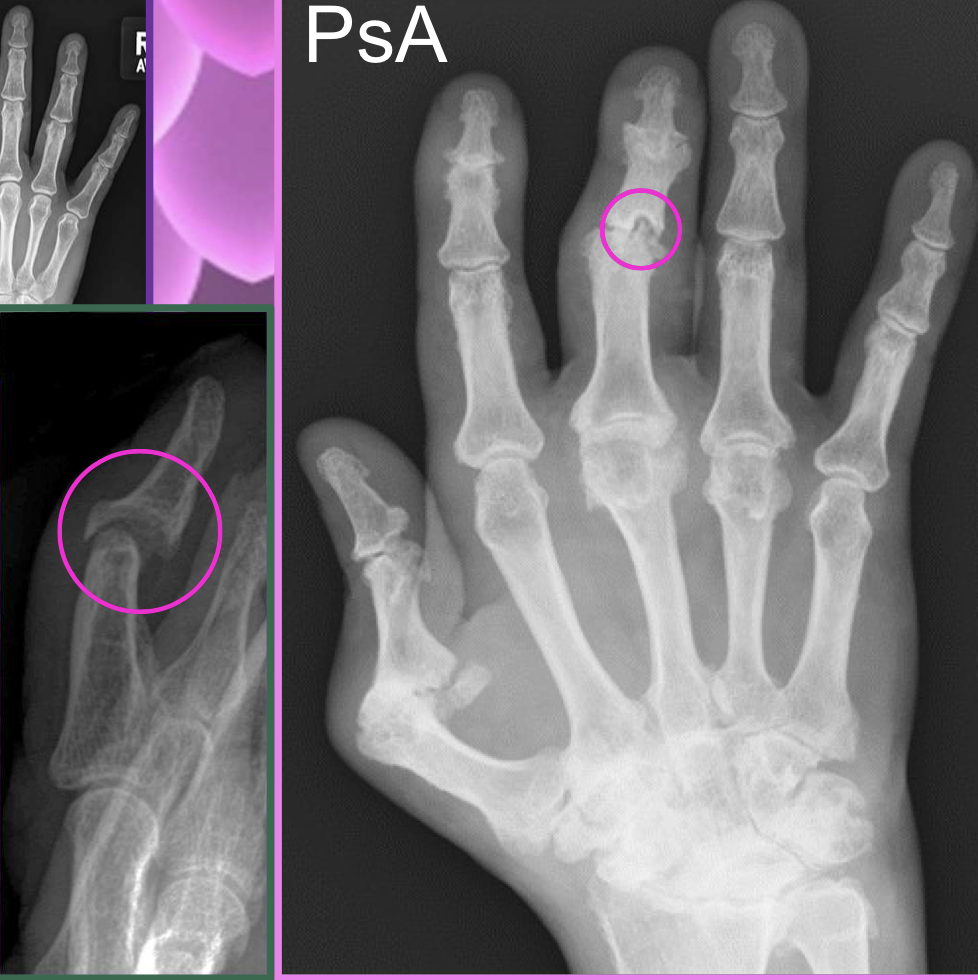

What type of characterisitcs of PsA are found in this image

soft tissue edema

nail pitting

JSN + central erosions (pencil in cup)

periostitis (lifted periosteum - mouse ears)